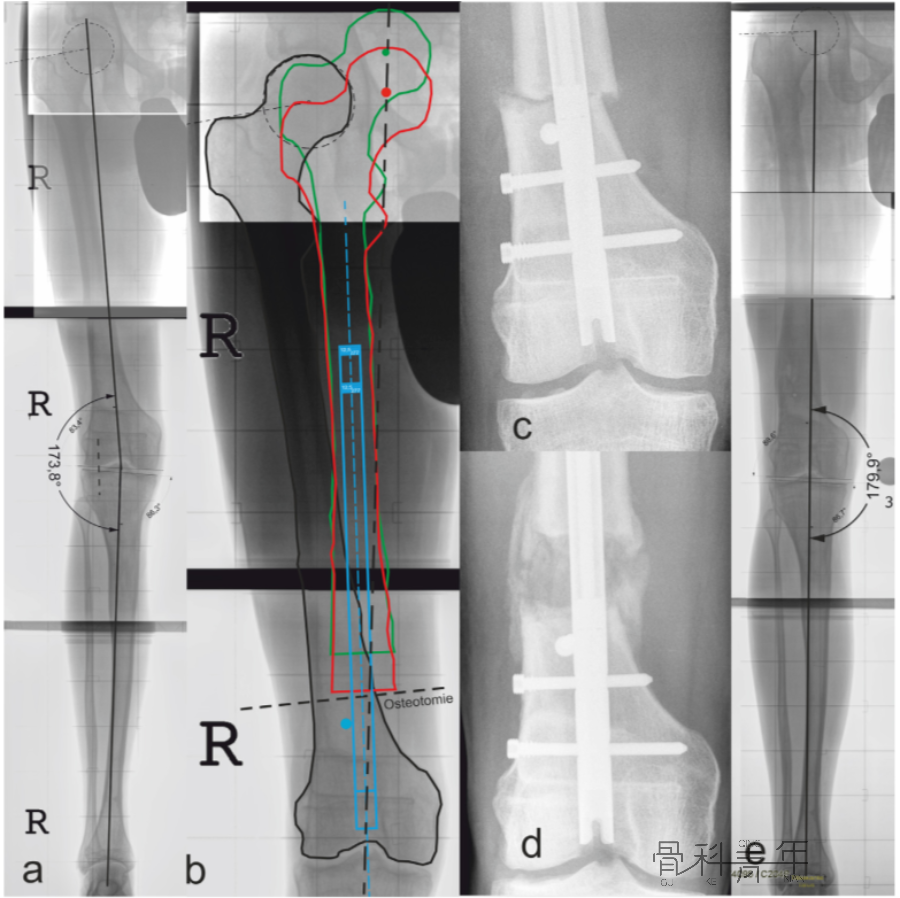

除了在骨折治疗中调整骨折的对线外,在下肢畸形矫正中,通过阻挡钉矫正髓内钉的位置,以达到同期手术完成多平面对线,也可取得良好效果。如下图所示:

为了矫正股骨力线,在干骺端横行截骨(a横行虚线)后,截骨远端移位,此时髓内钉置入后应为偏心方可维持矫形,为了获得髓内钉位置,需要置入阻挡钉(b)。

下图实际病例很好显示了阻挡钉的重要性:

图a所示该患肢与健侧相比,存在6.2°外翻和28mm短缩。图b红色轮廓为纠正力线后截骨近端的形态,绿色为同时纠正外翻和短缩后股骨近端的位置,依照绿色轮廓置入髓内钉,此时髓内钉进入截骨远端为偏心,为了维持髓内钉位置,阻挡钉置入位置明确。图d可见髓内钉及阻挡钉置入后情况。